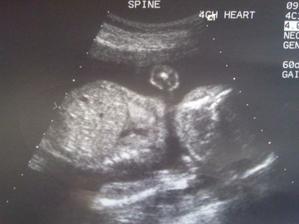

Velký UZ máme za sebou, dopadl dobře i když ještě za 14 dní jdeme na kontrolu, nevim proč, asi nebylo vše přehledné protože malej Kubík těsně před UZ usnul. Ještě nás pan Dr. poslal na doplnění UZ srdíčka. Jinak pěkně nám roste bříško, těhu probíhá bez problémů. Už máme pohyby od 28.6.2010 - to byly jen slaboučké a nevěděla jsem co to přesně je, ale 9.7.2010 mě poprvé Kubík lehounce kopl, teď už jsou pohyby pravidelný každý den, pěkně se mi vlní v bříšku. Tatínek taky zachtil jeden kopaneček 🙂

Tak kontrolu velkého UZ máme za sebou, dopadl dobře, nemáme žádné hrubé VVV. Na UZ srdíčka jsme už také byli, opět jdeme na další kontrolu 5.8.10, protože pan Dr. špatně viděl rozdělení obou komor...to neznamená, že by bylo něco špatně, ale Kubík nechtěl spolupracovat. Jinak vše ostatní je v pořádku a čekáme zdravého chlapečka. Výbavičku už také pomalu máme připravenu, už máme vybraný kočárek, postýlku ... už jen objednat. Rozhodli jsme se, že vše nakoupíme přes internet..... ebutik se ukázal jako spolehlivý el.obchod. Kočárek si koupíme na kocarky-tako

Dnešní kontrola srdíčka v UL dopadla dobře, čekáme zdravého chlapečka. Dnes přes ebutik objednána postýlka, komplet sada na postýlku, přebalovací podložka....a samozřejmě různé drobné zbytečnosti jak by řekl tatínek, ale maminka chce aby se malej Kubík měl jak v bavlnce 🙂